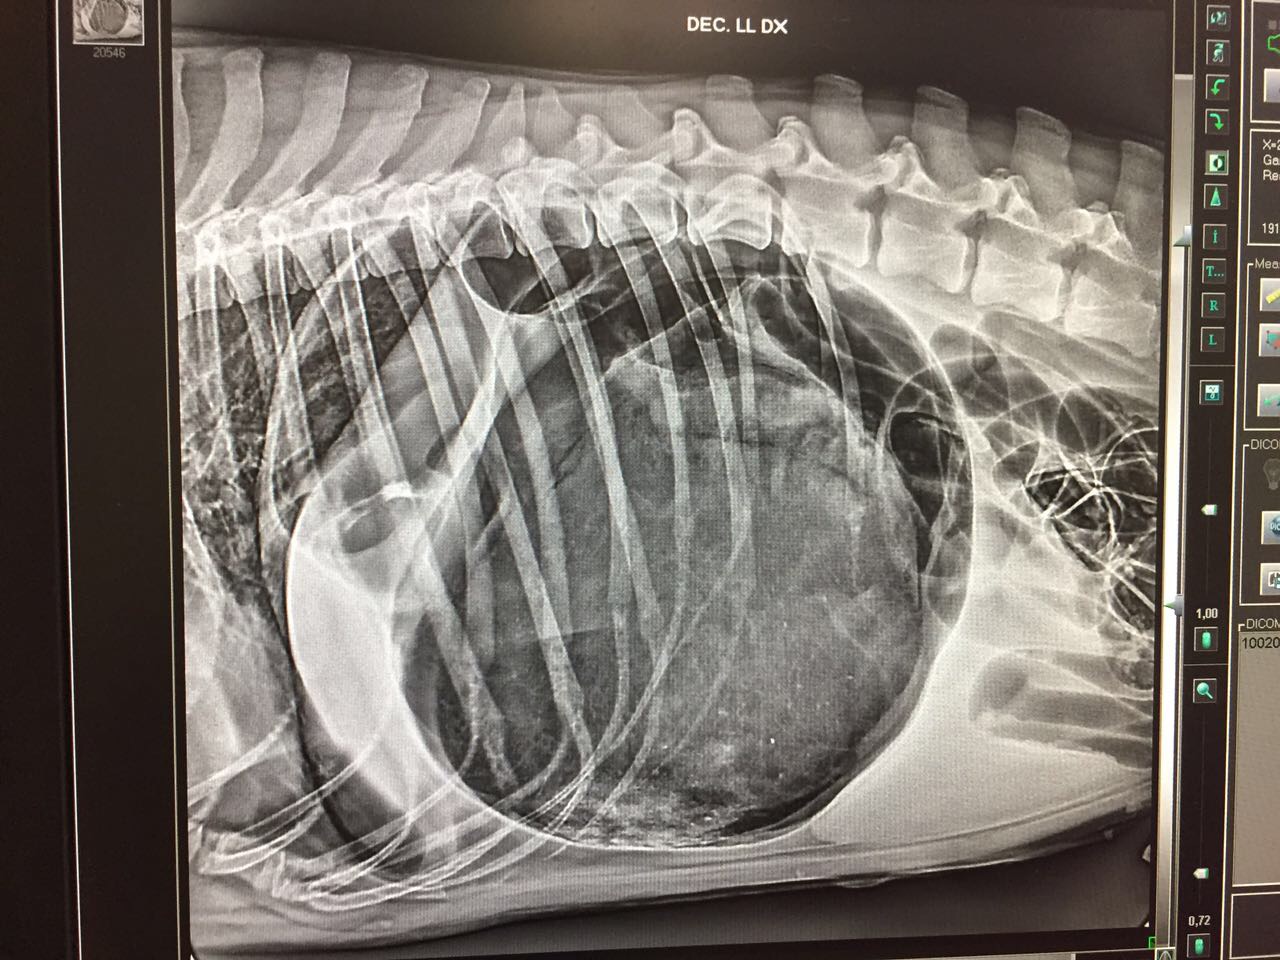

La patologia è caratterizzata dalla dilatazione dello stomaco, cui può seguire la torsione dello stesso attorno all'esofago con diversi gradi di gravità. Tra i sintomi più comuni vi sono i tentativi di vomito infruttuosi e la dilatazione dell’addome. In poco tempo, lo stomaco dilatato preme sul diaframma e sui grossi vasi sanguigni addominali ostacolando la respirazione e la circolazione e provocando un collasso. In mancanza di trattamento la patologia è mortale.